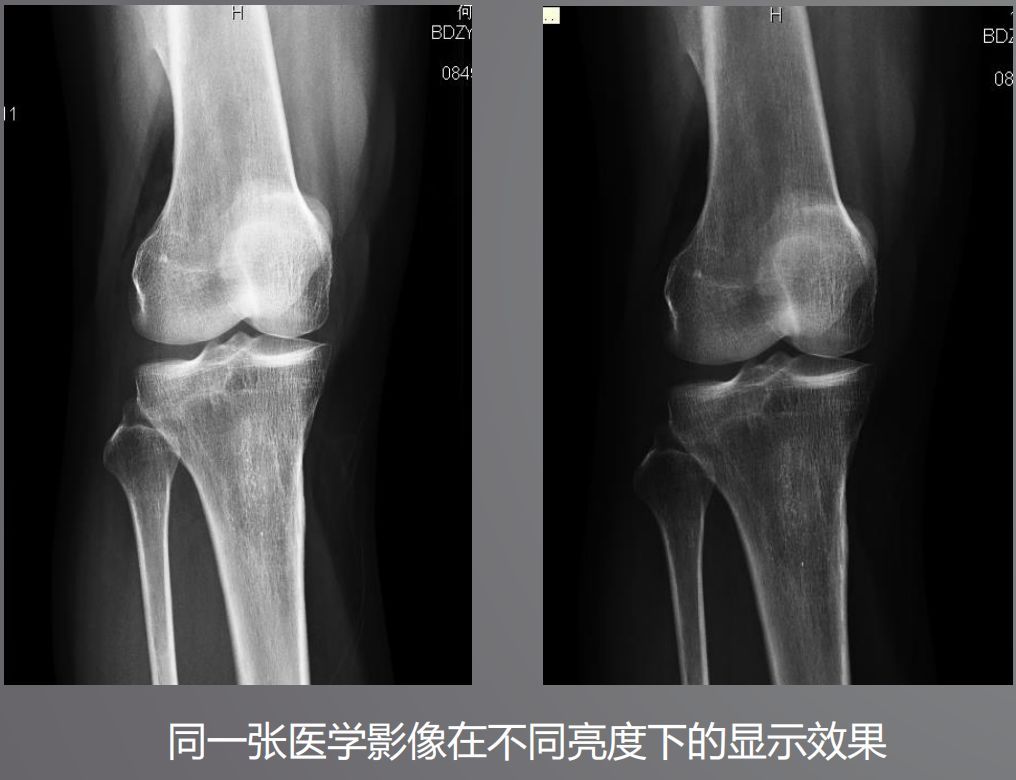

三、高亮度

高亮度從字面上就非常好理解了,回想在傳統膠片時代,閱片都是直接夾在大大的發光白板上。而平時我們瀏覽網頁或者看視頻并不需要那么高的亮度,導致普通顯示器亮度偏低,達不到醫用閱片的標準。

根據DICOM Part14規定,所有醫學顯示器必須符合GSDF的標準,確保顯示區域亮度符合一致性。而普通顯示器是不需要刻意符合這個標準的。

醫用顯示器通過系統測量和調整每一個像素的亮度,降低中心和角落之間亮度和色彩的不均勻性,通過減少這些差異,確保顯示器每個顯示區都能符合DICOM GSDF標準。